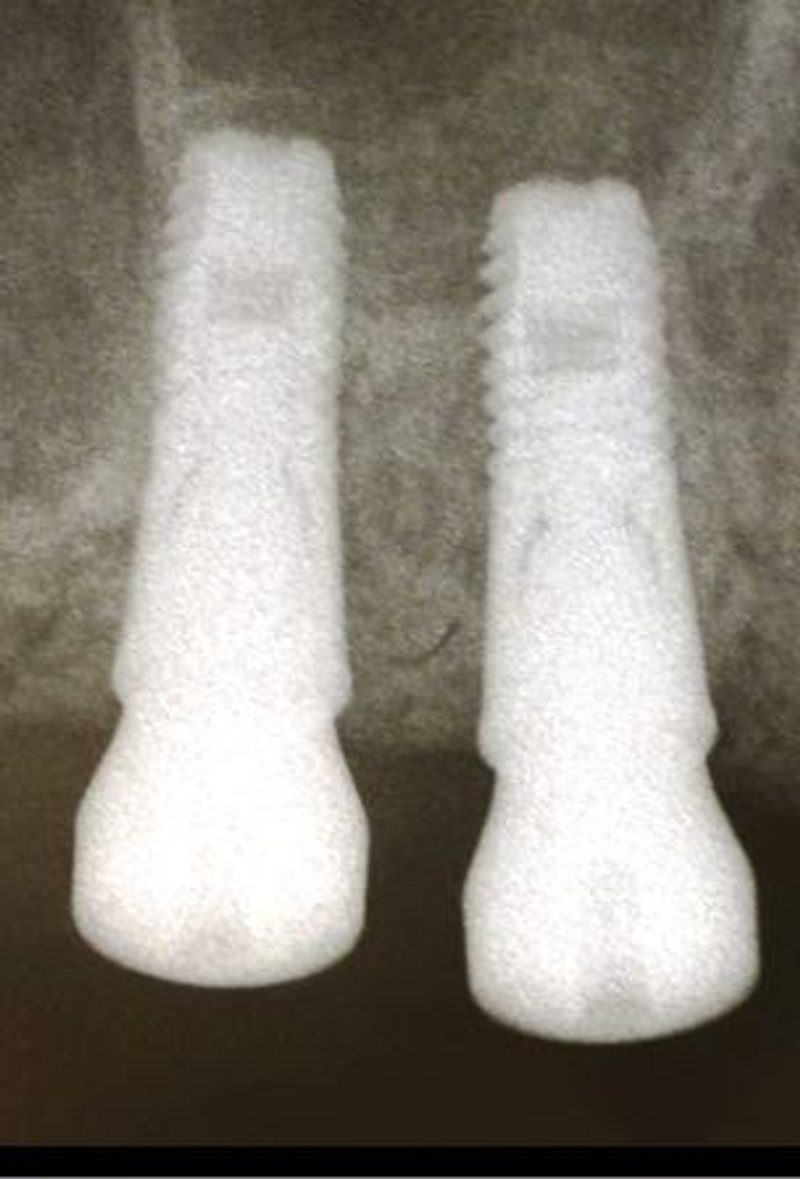

Вообще по идеи лучше всего конечно же ставить импланты ипортные!Ну и какие из этих надежнее или эстетичнее???![]()

Они намного надёжнее и эстетичнеее смотрятся, по сравнению с российскими имплантами!

Вы сами посудите, или через несколько лет будут чёрные проявления от мет.кер, или в течении многих лет, ровные белоснежные коронки, согласитесь есть разница и между раскуроченой десной и аккуратно высверленной для импланта!![]()

а рядом зарубежные показаны, вот наподобие что вы картинку мне показали и как выглядят уже готовая работа, поэтому я вот так и написала, эт не правильно???